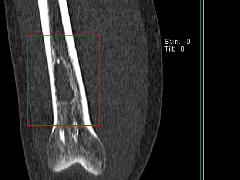

动脉瘤样骨囊肿是溶骨性的,通常是扩张的病变,最常见于长骨的干骺端。它们出现在较年轻的一组(通常在5至20岁之间),在年龄上与巨细胞瘤重叠较小。如果囊肿在骨膜闭合后发生或持续存在,那么它可能延伸到骨骺并且与巨细胞瘤无法区分(图9A)。CT或MRI可显示液体水平,代表血液分层(图9B)。缺乏增强固体成分也将支持巨细胞瘤与动脉瘤样骨囊肿的鉴别。

图9A-13岁女孩,动脉瘤样骨囊肿。照片显示肱骨远端近关节面的轻微可扩张的病变(箭头)。

图9B。-13岁女孩,动脉瘤样骨囊肿。T2加权冠状STIR图像显示具有多种液体水平(箭头)的多囊性病变,典型的动脉瘤样骨囊肿。